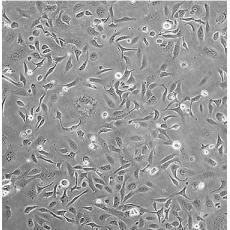

SK-OV-3 [SKOV3]

產品名稱 SK-OV-3 [SKOV3]

中文名稱 人卵巢癌細胞

組織來源 卵巢漿液性囊腺癌;腹水轉移;女性

生長特性 adherent

形態特征 epithelial

細胞描述 SK-OV-3 cells are resistant to tumor necrosis factor and to several cytotoxic drugs including diphtheria toxin, cis-platinum and adriamycin.